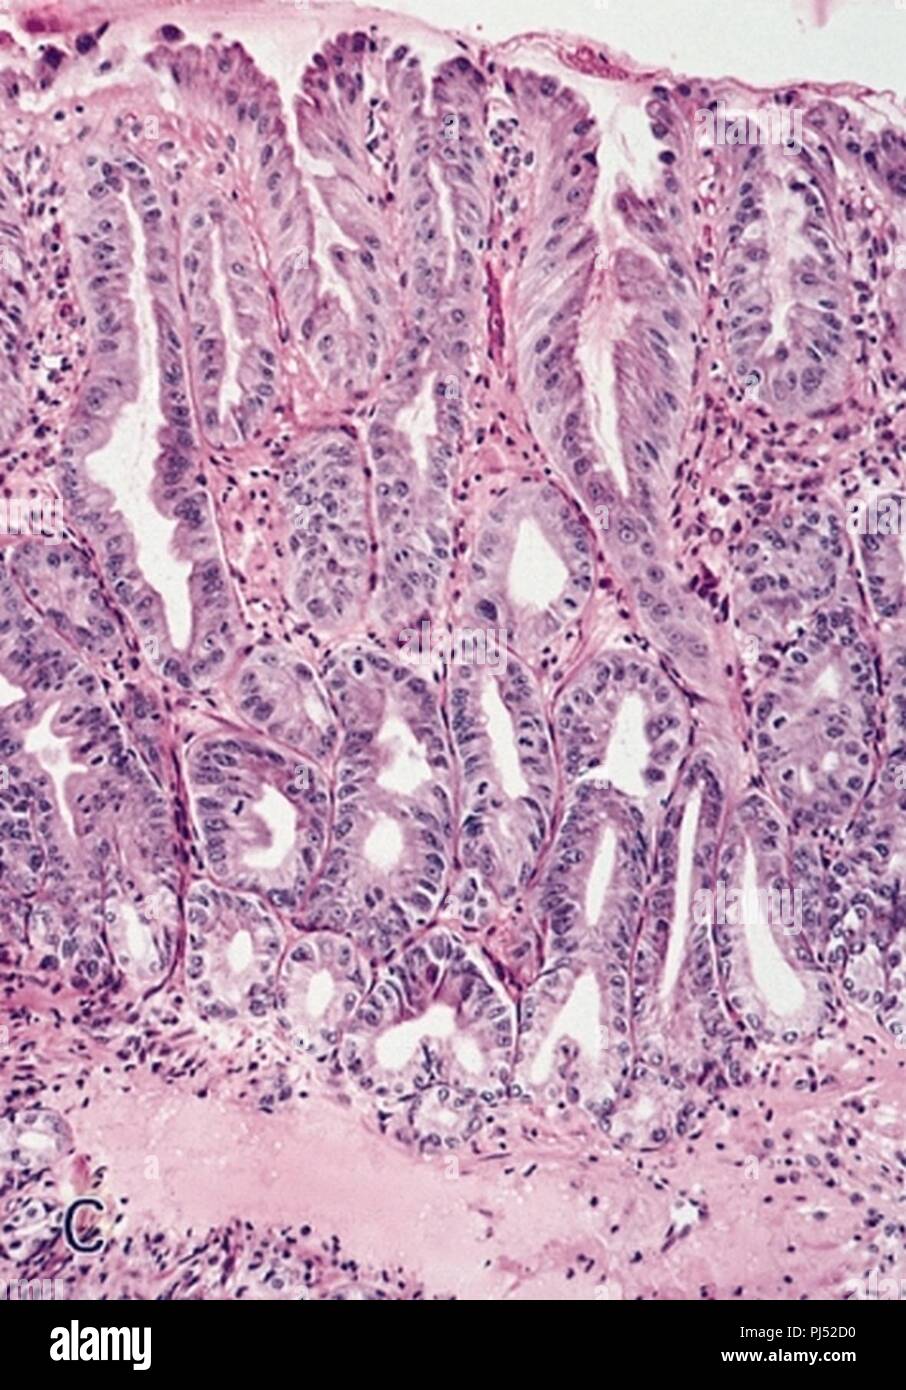

Barrett's esophagus with highgrade dysplasia. (A) and (B) This biopsy

Barrett's esophagus with highgrade dysplasia. (A) and (B) This biopsy Barretts With Dysplasia Order to address controversial issues in barrett’s oesophagus including definition, screening and diagnosis, surveillance, pathological grading for. If you have barrett’s esophagus, your pathology report will most likely mention dysplasia as well. Barrett’s oesophagus with dysplasia (abnormal cells) the treatment for barrett’s oesophagus has changed significantly over recent years. These cells normally look flat and are called squamous cells. Barrett's. Barretts With Dysplasia.